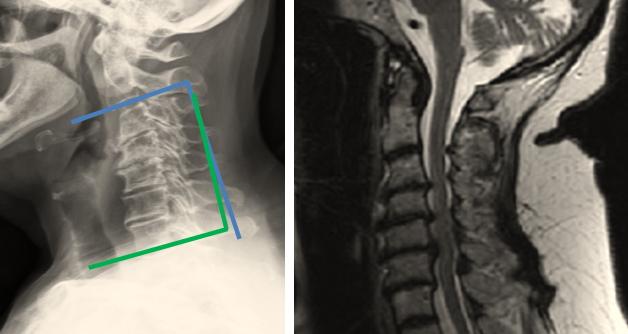

9. A 52-year-old male is involved in an altercation where his neck was twisted and extended with force. Upon presentation he complains of neck pain, and loss of ability to stand or ambulate. On physical exam, he has Grade 3 motor strength in the majority of his muscles groups in his upper and lower extremities. His sensory is intact in all four extremities, and his bulbocavernosus reflex is intact. Sagittal and coronal computed tomography are shown in Figure A and B respectively. The patient's neurologic condition is best classified as?

FIGURES: A

B

DISCUSSION: This patient has a spinal cord injury as a result of a rupture to his transverse ligament. This is evidenced by the increased atlanto dens interval on his computed tomography. Motor and sensory function are preserved below the neurological level, and at least half of key muscles below the neurological level have a muscle grade of 3 or more. His bulbocavernosus reflex is intact, so we know he is no longer in spinal shock. Therefore, he would be classified as an ASIA D.